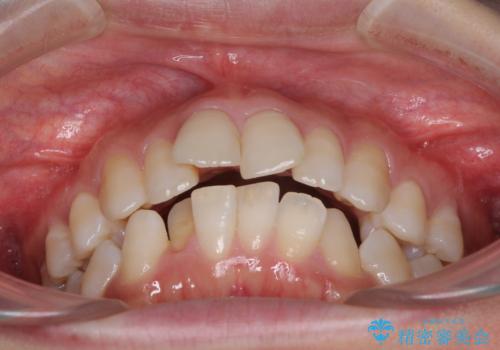

- 上の前歯の飛び出した感じと上下前歯のデコボコを気にして来院された患者様です。

叢生が強く、口元の突出感もあるため、上顎左右第一小臼歯4本を抜歯することとしました。

奥歯の咬み合わせ改善が必要なため、ワイヤー装置による矯正治療を強くお勧めしまたが、本人の希望でインビザラインにて治療を開始することとなりました。

インビザラインでの抜歯治療は予定通りに治療が進まないことが多いため、必要であればワイヤー矯正に切り替えるとお伝えした上で治療を開始しました。